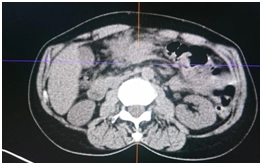

ПЭТ/КТ

Гиперметаболический процесс в утолщенных стенках ободочной кишки и окружающей клетчатке – может соответствовать опухолевому процессу.